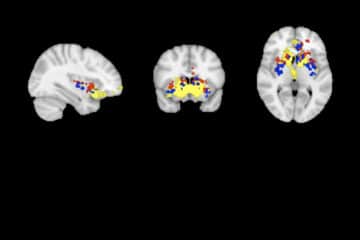

Cerveau : les différences gauche-droite cartographiées

Published on 19 October 2022

Article dans “Cerveau et Psycho” par Emmanuel Mellet et Michel Thiebaut de Schotten